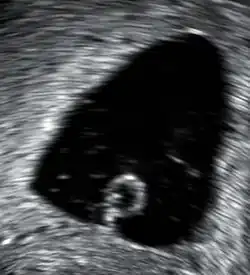

A 13-week fetus without cardiac activity located in the uterus (delayed or missed miscarriage)

A missed miscarriage is when the embryo or fetus has died, but a miscarriage has not yet occurred. It is also referred to as delayed miscarriage, silent miscarriage, or missed abortion.[30][115]